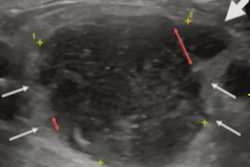

The researchers sought to compare the sensitivity and specificity of ultrasound to MRI in the diagnosis of bone stress injury through a study that included 37 young adult athletes presenting in an academic sports medicine clinic between 2016 and 2020 with suspected lower extremity bone stress injury. Sports included everything from crew, field hockey, gymnastics, and running to soccer, tennis, track, and volleyball. All patients underwent MRI and ultrasound exams.

Of the 37 study participants, 30 (81%) had bone stress injuries. The most common injuries were in the metatarsal bones (54%) and the tibia (32%).

Ultrasound scored relatively high across a range of performance measures relative to the gold standard of diagnosis on MRI scans, the group found.